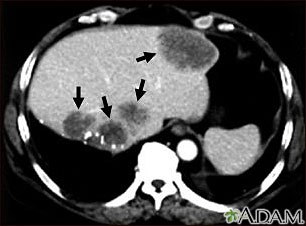

A CT scan of the upper abdomen showing multiple metastasis (cancer that has spread) in the liver of a patient with carcinoma of the large bowel. Note the dark areas in the liver (left side and center of picture).